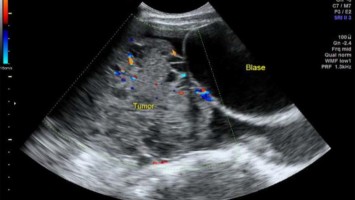

Worauf man bei der Sonografie von Adnexbefunden achten sollte

Die Abgrenzung zwischen benignen und malignen Veränderungen anhand des transvaginalen Ultraschalls wird hierzulande noch immer unterschätzt. Worauf Sie achten sollten und welche Schritte bei einem Befund zu unternehmen sind, lesen Sie hier.